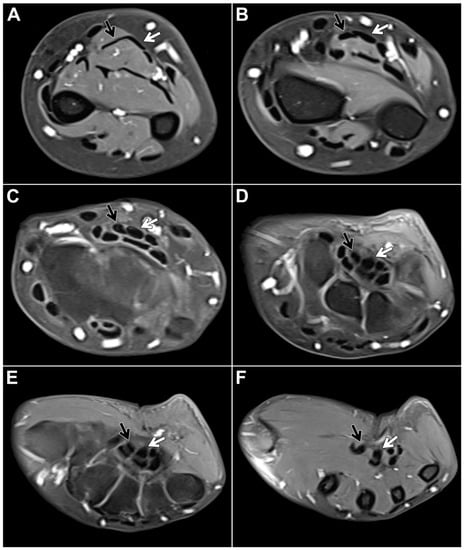

3.2. MRI-Based Flexor Digitorum Superficialis Assessment

Within the study sample, the chiasma antebrachii with the above-described anatomical features was identified in 88 patients (98.9%). We defined the proximal margin of the chiasma as the first axial slice where the distal FDS/2 tendon was depicted inferiorly to the FDS/3 tendon and the distal margin as the first axial slice when the two tendons could be depicted horizontally adjacent to each other again (Figure 2). Measured according to these parameters, the chiasma antebrachii had a median length of 28 mm (IQR: 24 mm–35 mm). Next, we assessed the location of the chiasma in the forearm in relation to the distal radioulnar joint and the elbow joint. We measured the respective distance from the proximal margin and documented a median distance to the distal radioulnar joint of 16 mm (IQR: 8 mm–25 mm) and a median distance to the elbow joint of 215 mm (IQR: 187 mm–227 mm). Measurements were performed based on axial images but were correlated in at least one other standard plane. In only one patient, the intersection was located in the middle part of the forearm. In this particular case, the intermediate tendon of the FDS crossed under the FDS3 from the ulnar to the radial side. As a consequence, the distal FDS tendon segments for digits 2 and 3 could be depicted running parallel to each other in the distal third of the forearm up to their insertions at the mid phalanx of digits 2 and 3, with the FDS/2 located more radially (Figure 3).

Figure 2. Fat-suppressed T1-weighted left forearm scan after intravenous administration of gadolinium-based contrast agent in a 48-year-old woman for presumed compression of the median nerve, which is located directly on the palmar side of the FDS tendons. Axial planes ((A,B): forearm level, (CE): carpal tunnel level, (F): midcarpal level) depict the most common form of flexor digitorum superficialis anatomy: From the ulnar side of the forearm, the FDS/2 tendon (black arrow) crosses over the FDS/3 tendon (white arrow), thus forming the chiasma antebrachii.